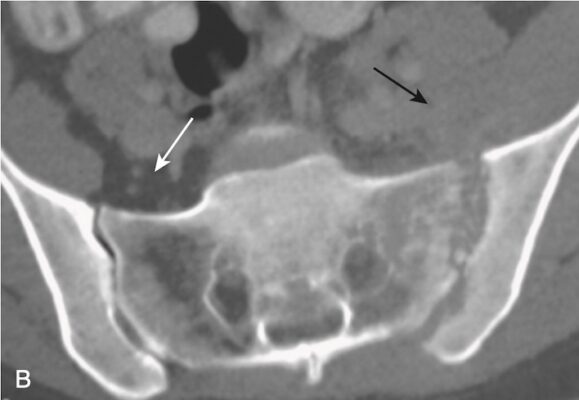

Cận lâm sàng

Không có thăm dò hình ảnh học nào có giá trị hoặc đáng tin cậy cho RLCN KCC. Mục đích thăm dò chẩn đoán hình ảnh là để đánh giá các chẩn đoán thay thế. Chụp X quang thường có thể phát hiện đau KCC do các nguyên nhân về xương gây ra, chẳng hạn như viêm khớp do nhiễm trùng, viêm nhiễm, thoái hóa. Scan xương và chụp cắt lớp vi tính có thể phát hiện những thay đổi của xương do gãy xương, nhiễm trùng, khối u, viêm khớp. Hình ảnh cộng hưởng từ có thể phát hiện những tình trạng này cũng như các bệnh lý mô mềm và những thay đổi tủy xương trong viêm khớp cùng chậu với các ăn mòn liên quan của nó. Siêu âm có thể được sử dụng để phát hiện những thay đổi bệnh lý bên trong cấu trúc dây chằng phía sau của KCC, là nguồn có thể gây đau. Tuy nhiên, thường gặp RLCN KCC với hình ảnh học bình thường, và do đó RLCN KCC thường được xác định dựa vào lâm sàng.